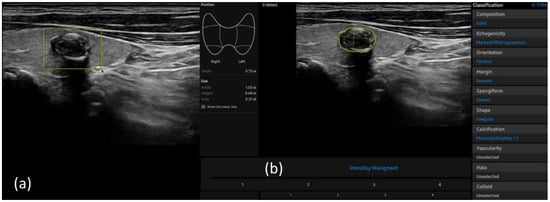

2.4. S-Detect